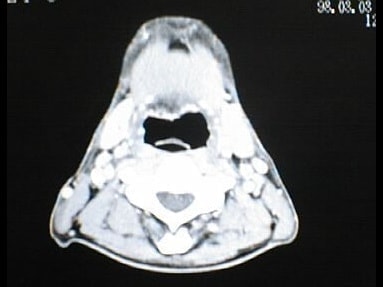

末期がん宣告時と末期がん消滅時の診断画像比較

ここでは、末期がんと宣告された時のCT&MRI画像と、その約3か月後の末期がん消滅時の画像を比較して頂けます。(写真左が「末期がん宣告時の画像」、写真右が「末期がん消滅後の画像」)

CT画像比較

中咽頭末期がんCT画像②

入院当時CT画像②

中咽頭末期がん消滅CT画像②

入院3か月後癌消滅CT画像②